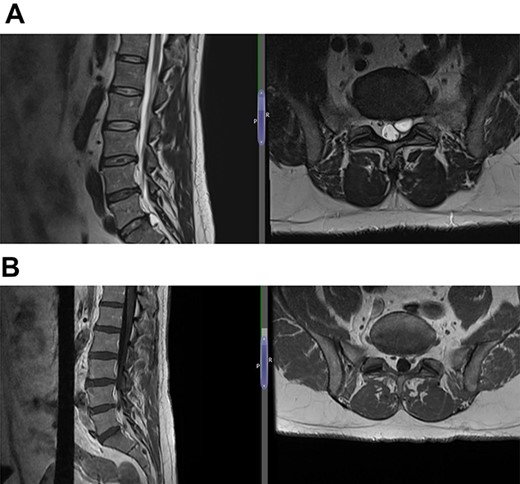

(A) Case 3—an early MRI demonstrates at L5/S1 level moderate diffuse disc bulge is seen with early bilateral facet joint degenerative changes; there is irritation of the L5 nerve roots bilaterally, and at L5/S1 level moderate left posterolateral disc bulge is seen irritating the S1 nerve roots bilaterally left more than right, and bilateral facet joint degenerative changes also noted at this level, and (B) case 3—a later MRI, the cystic changes noted at the L4-L5 level which clearly shows a connection with the intervertebral disc.